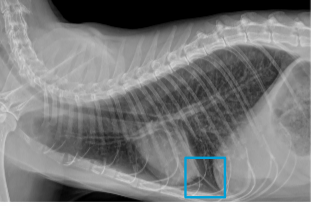

• what can be noted in the blue box?

air trapping

• the cardiac silhouette and diaphragm should touch on radiograph, if they do not then this is indicative of air trapping

• Airway obstruction occurs due to bronchoconstriction, inflammation and mucus plug in narrowed bronchioles. Air trapping leads to the destruction of alveoli. The end result is chronic damage that is irreversible due to remodelling.